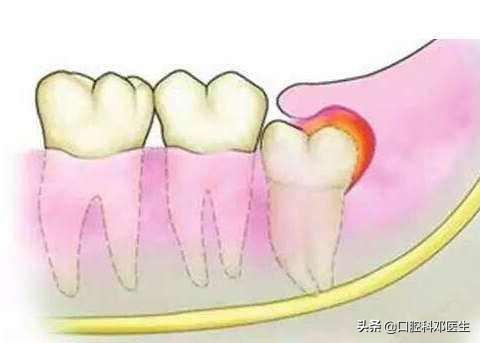

2.智齿本身蛀牙或者引起邻牙蛀牙的智齿

由于智齿比较靠后,卫生很难搞到位,因此很容易蛀牙,或者智齿位置不好,容易塞牙,引起邻牙蛀牙,这样的智齿一般都不建议补牙,直接拔掉就可以啦!